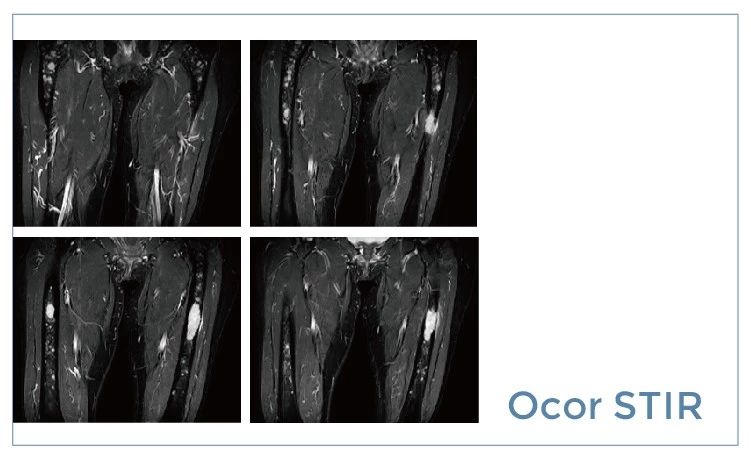

【朗润影像档案】磁共振影像病例分享(编号20190712)